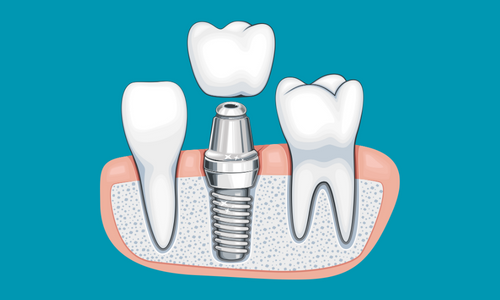

Bununla birlikte, teknolojiye ve yenilikçi uygulamalara verdiğimiz önem de bizi farklı kılan unsurlardan biridir. Tosun Diş

Kliniği olarak, en son diş tedavisi tekniklerini ve ekipmanlarını kullanarak, hastalarımıza en iyi sonuçları sağlamak için

sürekli olarak kendimizi güncelliyoruz. Bu sayede, güvenilir, etkili ve konforlu bir tedavi deneyimi sunarak fark

yaratıyoruz.